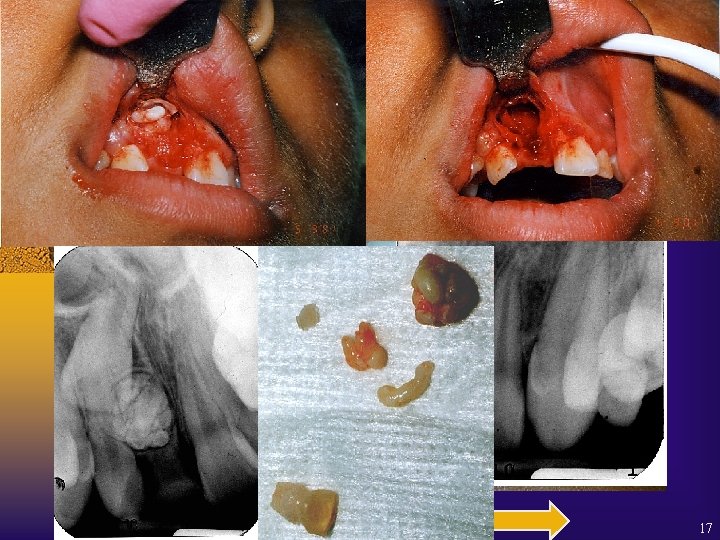

17